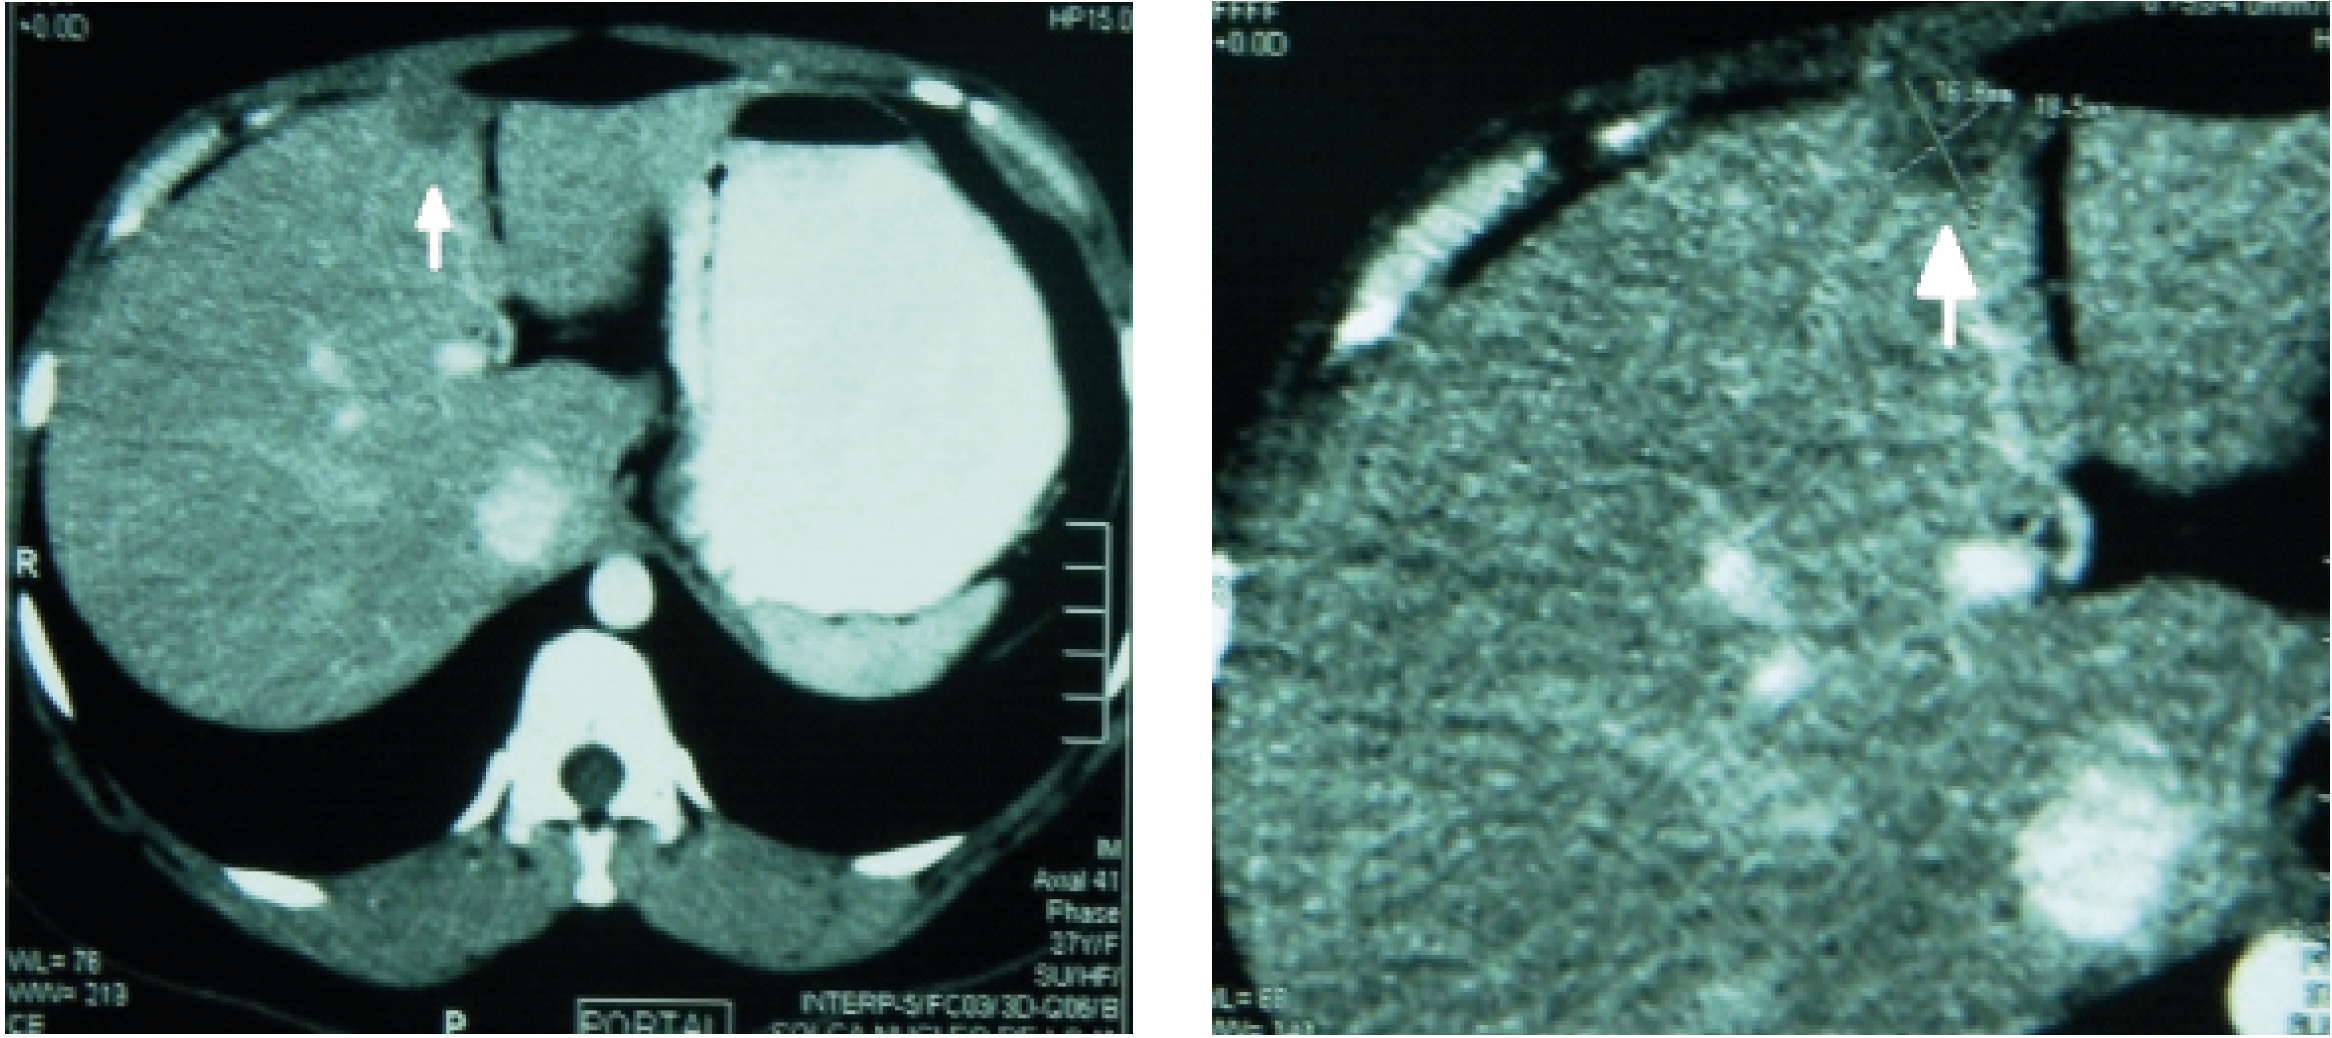

Se realizan estudios de extensión, donde se identifican estructuras internas normales en la tomografía de tórax, en el encéfalo y en el esqueleto. En la tomografía de abdomen, se detecta hígado de densidad heterogénea por presencia de imagen hipodensa de forma redondeada, con bordes definidos de 18.5 mm con 25 UH, que incrementa su densidad con el medio de contraste a 65 UH.

Figura 1. Se aprecia la lesión hepática en tamaño normal y ampliado.

Se asume que se trata de un cuadro de cáncer de mama con recidiva locorregional severa y metástasis hepática.